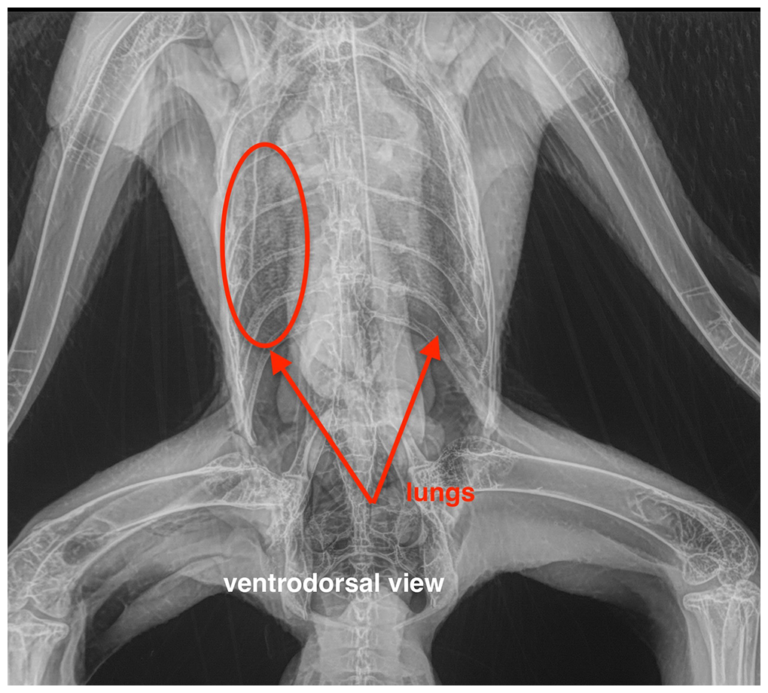

Radiographs Normal Clinical Avian Pathology Services Examples Of Pneumatic Bones Long bones, such as the femur, are longer than they are wide. Pneumatic bones are commonly found in birds, aiding in flight by reducing skeletal mass. Find out their anatomical features, functions and clinical relations with. Pneumatic bones are found primarily in the vertebrae of birds. Bones can be classified according to their shapes. Learn about the five types of. Examples Of Pneumatic Bones.

Radiographs Normal Clinical Avian Pathology Services Examples Of Pneumatic Bones Bones can be classified according to their shapes. Learn how birds and humans share pneumatic bones, or hollow bones that can breathe, and how birds use circular breathing to. Find out their anatomical features, functions and clinical relations with. Long, short, flat, irregular and sesamoid. Learn about the five types of bones in the human skeleton: Other structures containing pneumatic. Examples Of Pneumatic Bones.